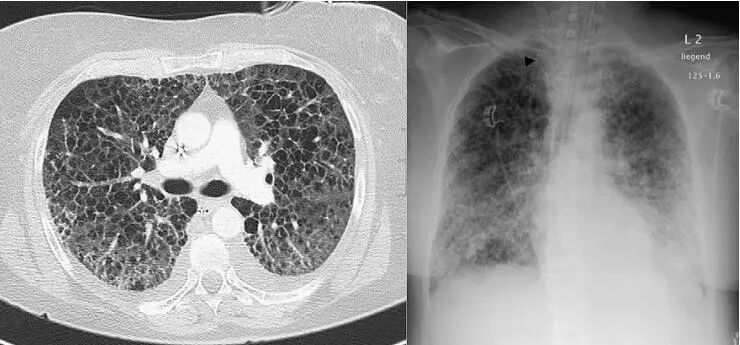

下面这个患者就更不典型了:

什么情况?这不是朗汉斯组织细胞增生症?不是淋巴管平滑肌瘤?

NO 。

小叶间隔增厚,磨玻璃影,流感肺炎。

并且,居然有少量胸水!难得难得!

The patient underwent extracorporeal membrane oxygenation (ECMO) therapy 4 days after hospitalization.

入院后第4天,不得已用了ECMO治疗。

实变,多发,磨玻璃,晕征,呼吸困难,病毒性肺炎。

The patient was admitted to the intensive care unit and underwent extracorporeal membrane oxygenation (ECMO) therapy 2 days after hospitalization.

这个病人更严重,有糖尿病,入院后2天就不得已用ECMO治疗。